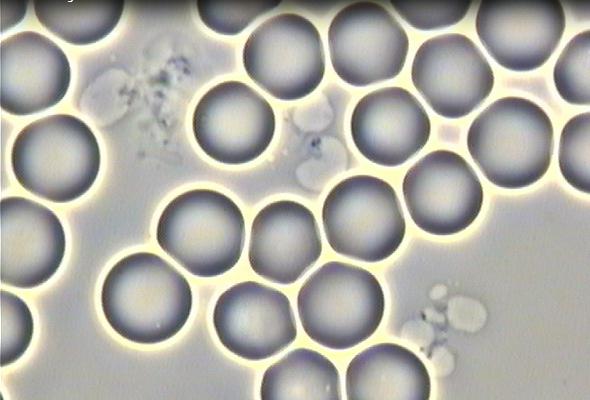

These included complete reversals in conditions such as tendinopathy, osteoporosis (OP), chondromalacia patellae (CMP), hypertension (HTN), pre-diabetes, chronic fatigue syndrome (CFS), osteoarthritis (OA), degenerative disc disease (DDD), cellular agglutination, urinary tract infections (UTI), and stage-3 chronic kidney disease (CKD3). The regenerative results were often accompanied with supportive medical documentary evidence.

In 2012, Creed disclosed his microscopic before/after blood analyses to the Human Performance Laboratory of the Naval Special Warfare (NSW) Group 2 Training Detachment (TRADET) and revealed definitive proof of the adverse agglutinating effects of gluten on red blood cells.

Before-and-after images of Creed’s red blood cells in response to specific dietary changes